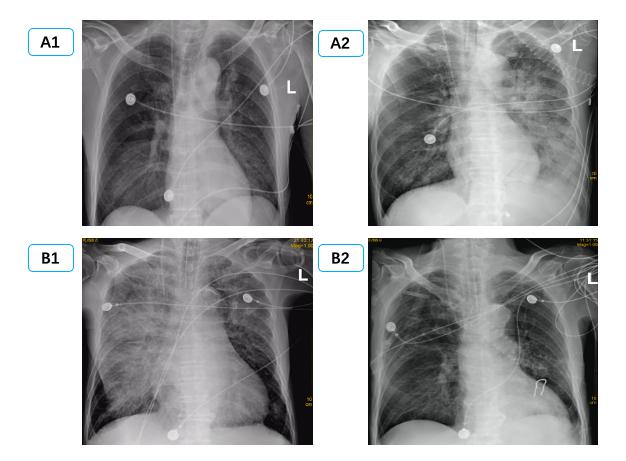

由于单侧PE病情轻重不一,影像表现可以为间质B线、毛玻璃影,严重可表现为肺实变,因此常误诊为肺部感染、肺出血、支气管扩张、肺实变等[29-31]导致病情延误。本研究中有12例单侧PE患者初次影像报告未准确识别; 因此建立重复可量化的单侧PE影像定义及分级标准有组于单侧PE诊断[32]。有心脏病史,心脏超声提示长期二尖瓣反流,长期有右侧胸腔积液,结合入院后床边BNP及肺部超声可以进行鉴别,尤其是床边重症超声可以及时发现明显二尖瓣反流,及时监测肺部超声表现可予以鉴别诊断。如图 4中B患者,入院前肺部CT正常,因失血性休克导致心脏骤停3 h后胸片提示右侧渗出加重,肺部超声由A线为主逐渐发展为B7线、B3线、融合B线及肺实变,提示患者PE程度逐渐加重; 同时心脏超声提示新发重度二尖瓣反流,综合考虑诊断单侧PE,经呼吸支持,利尿治疗后患者胸片、肺部超声均迅速恢复正常。而长期心衰合并二尖瓣反流患者,联合下腔静脉、颈静脉等超声进行容量评估,可与肺部感染相鉴别[33]。急性胸痛患者肌酸激酶同工酶联合床边及时检测肌钙蛋白,可早期诊断心肌梗死,为诊断心源性PE提供依据,本研究中两组间心肌损伤标志物差异无统计学意义。

| 图 4 患者B胸片及肺部超声改变过程 Fig 4 X-ray and lung ultrasound image of patient B |